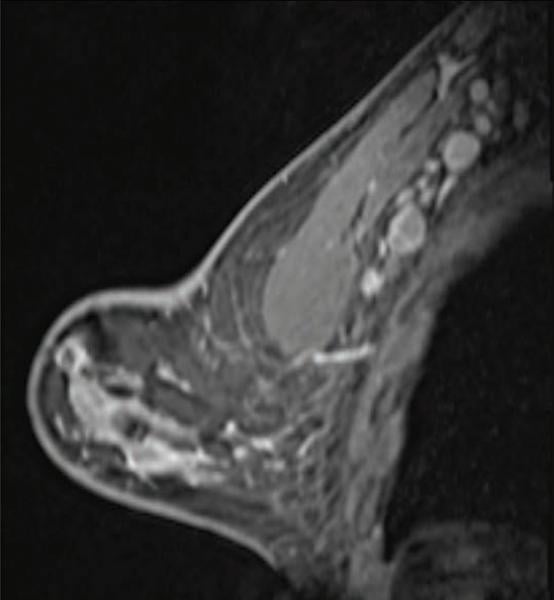

This photo gallery shows the variety of radiological presentations of COVID-19 (SARS-CoV-2) in medical imaging, including computed tomography (CT), radiograph X-rays, ultrasound, echocardiograms and magnetic resonance imaging (MRI). The radiology images show examples of typical COVID pneumonia in the lungs and the numerous complications the virus causes in the body in multiple organs, including the brain, kidneys, heart, abdomen and vascular system.

Ultrasound, especially hand-held ultrasound imaging devices, have become a primary imaging modality for novel coronavirus because of the ease to bag the device and sterilize it after use. CT and mobile X-ray systems are also used as front-line imaging systems for COVID-positive or suspected COVID patients.